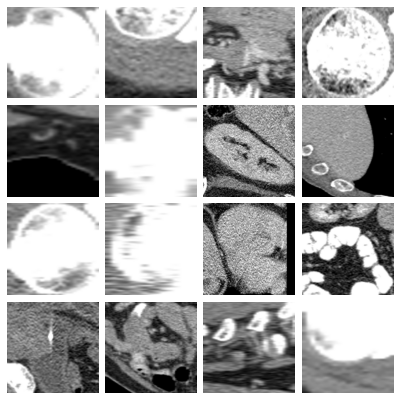

- organs_axial, Axial Organ Slices:

-

Dataset of axial image slices of 11 different organs, extracted from the Liver Tumor Segmentation Benchmark (LiTS) dataset [bilic2023liver] and the corresponding organ bounding box annotations from [xu2019efficient]. We derived a multi-class organ classification task with 11 labels by extracting a cropped image of each individual organ in each of the CT volumes using the bounding box annotations. We obtained a total of 1,645 organ images images. We removed 106 images for which the voxel size information was missing. The axes on one image were permuted to bring it to the same format as the other images. The images and masks were sliced from the original 3D volumes by taking the center of the organ bounding box in the axial plane. The Hounsfield-Units of the images were transformed into grayscale images by applying a window with a width of 400 and a level of 50, which are typical values for abdominal CT imaging. The images and masks were cropped to a square size in the physical space, by centering at the center of the bounding box and expanding the smaller side. The resulting images and masks were resized to pixels using bi-cubic and nearest neighbor interpolation, respectively. For visualization purposes, we additionally provide images averaged over the 10% central slices with the projected bounding boxes of all organs extracted from the image drawn on top.

- organs_coronal, Coronal Organ Slices:

Dataset of coronal image slices of 11 different organs, extracted from the LiTS dataset. The images were processed the same as described for the Axial Organ Slices dataset, except that the coronal projections were used.

- organs_sagittal, Sagittal Organ Slices:

Dataset of sagittal image slices of 11 different organs, extracted from the LiTS dataset. The images were processed the same as described for the Axial Organ Slices dataset, except that the sagittal projections were used.